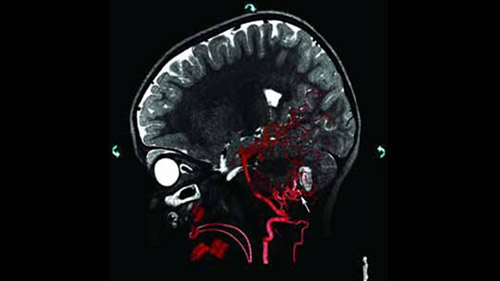

MR/CT Roadmap visualizes lesion boundaries and corresponding vascularization, while helping you to manage X-ray dose and contrast medium. 3D Roadmap provides full 3D view for dynamic guidance of guidewire and catheter navigation through complex vascular lesions.

Integration of multi modality imaging using pre-acquired MR/CT potentially can help to increase efficiencies.